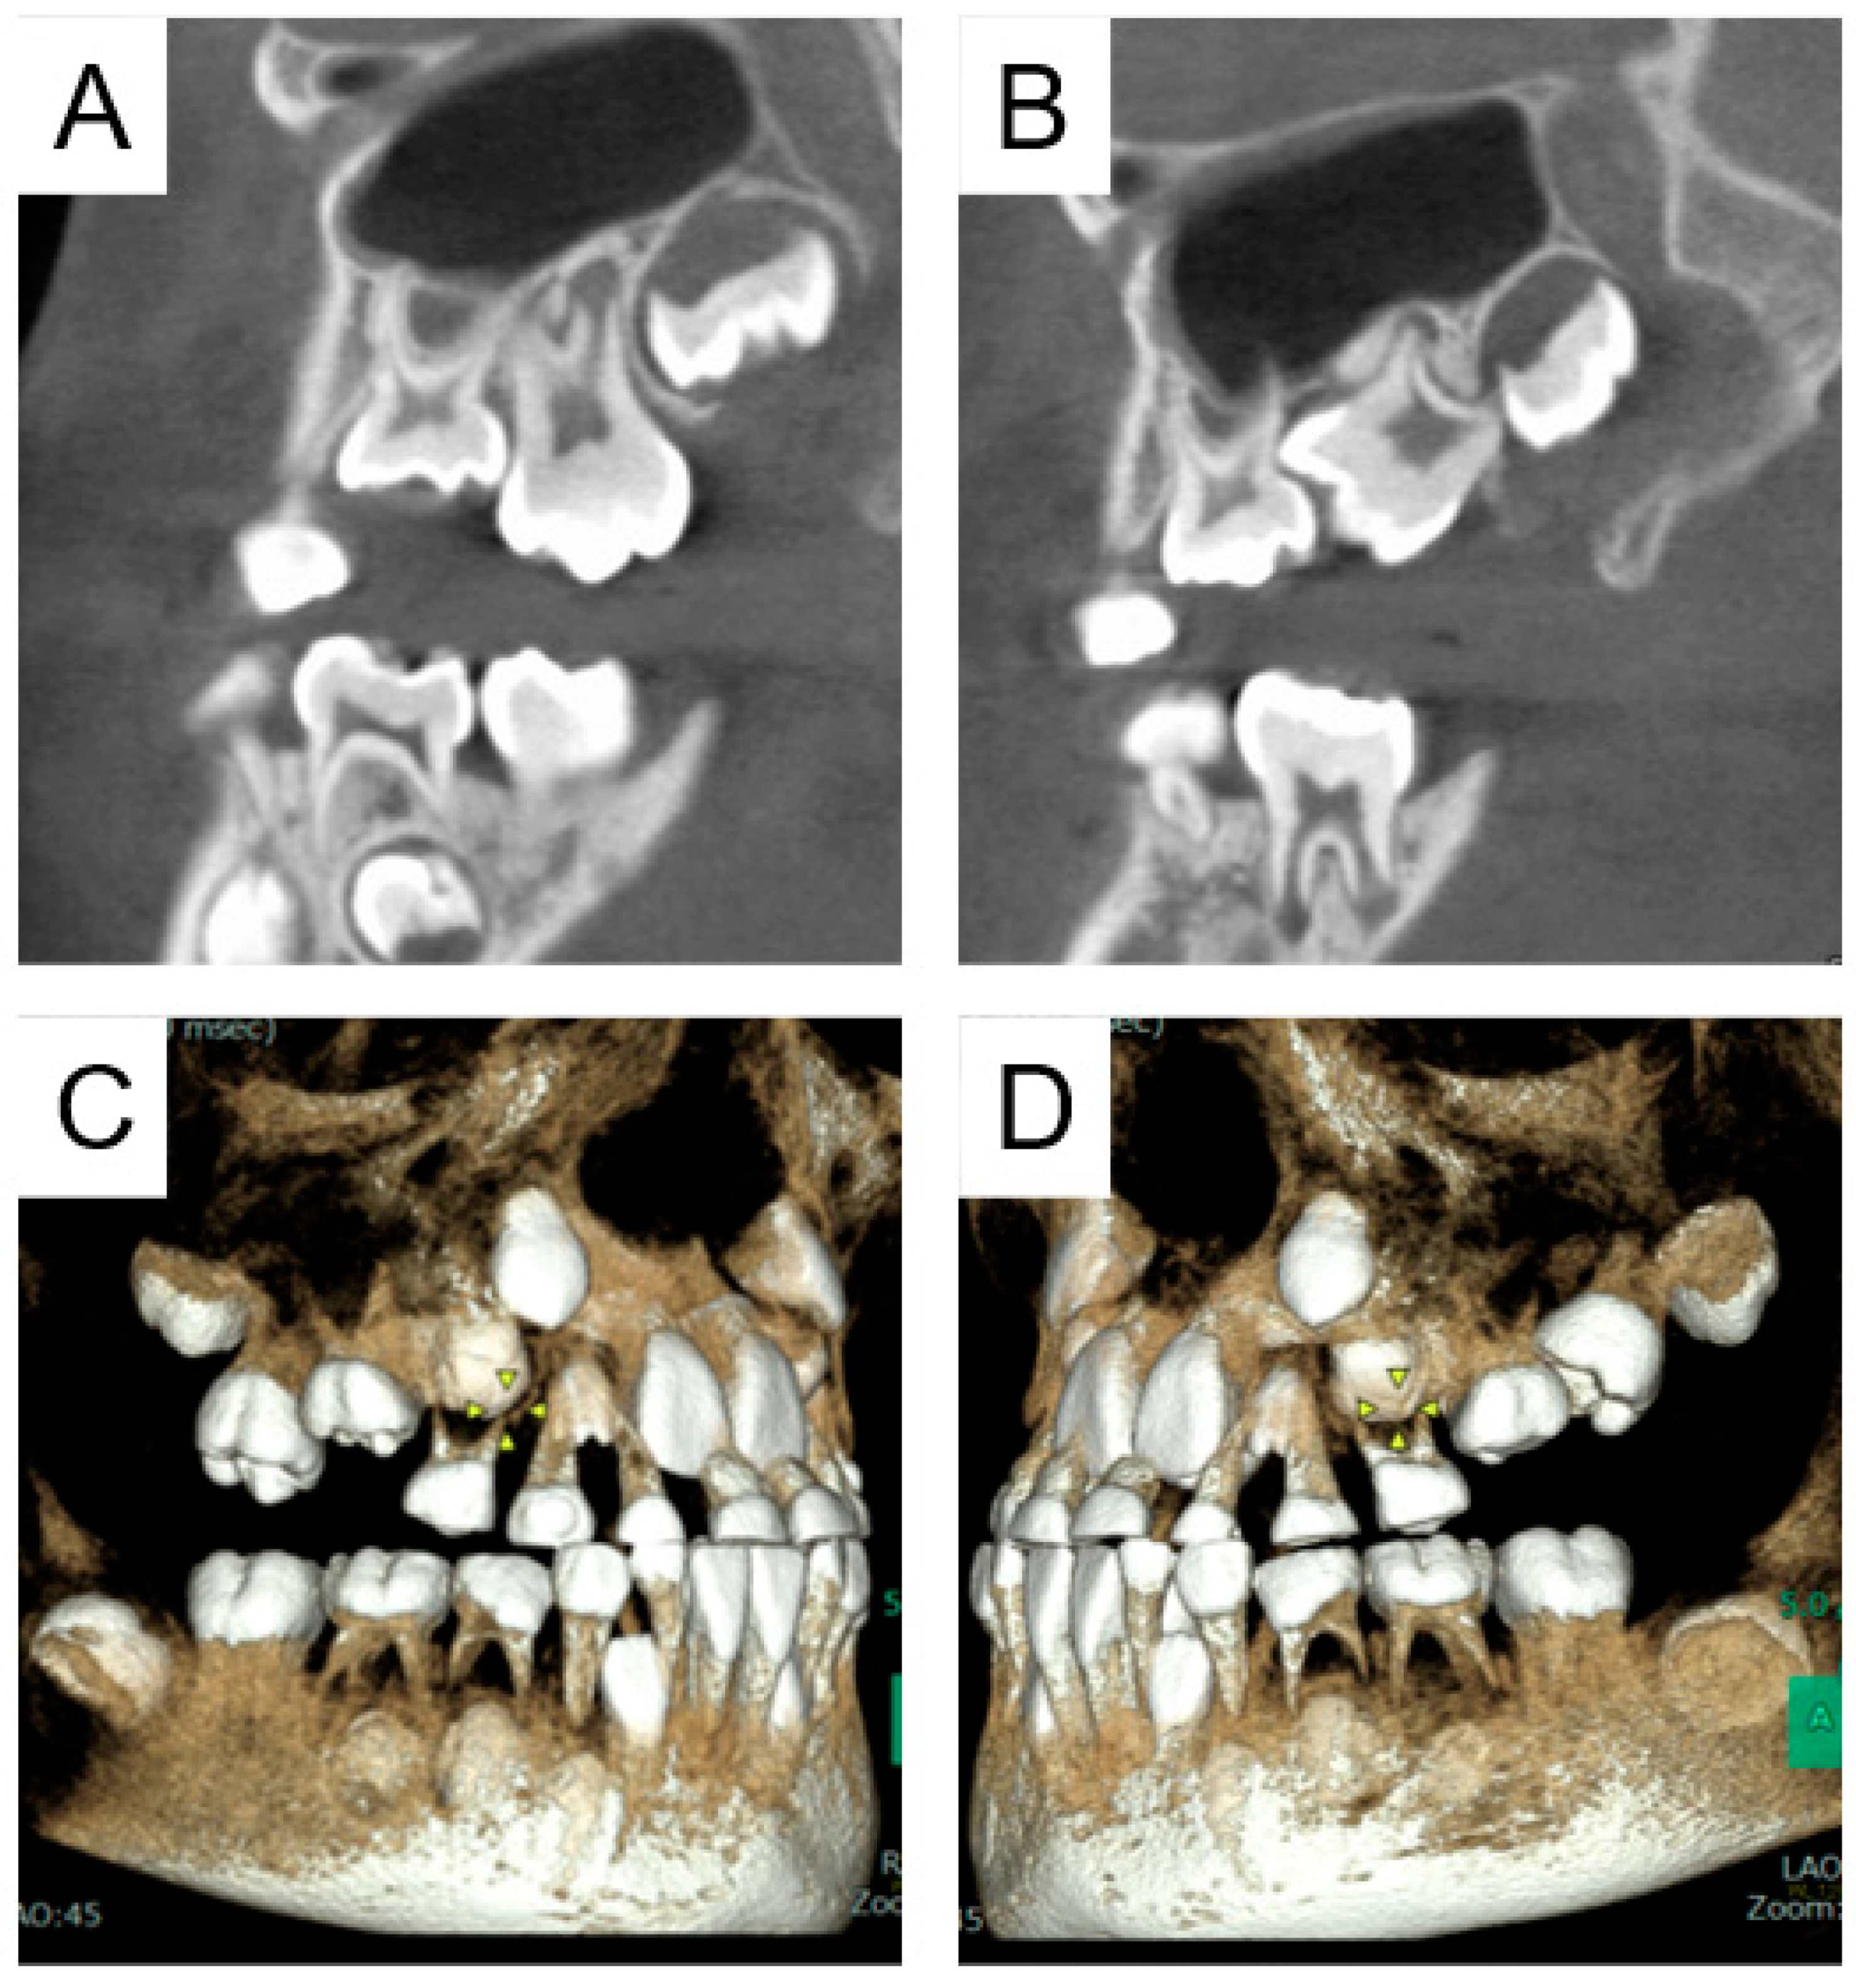

2.1. Case 1

2.2. Case 2